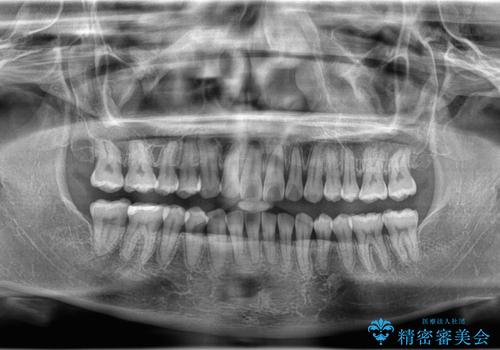

下顎前歯の叢生がとれ右上2の反対咬合も改善し患者様にも満足していただけました。治療期間は1年~1年半を見込んでいましたが、患者様の協力もあり10か月で矯正を終えることが出来ました。

インビザラインはご自身でマウスピースをはめて頂く矯正なので、マウスピースの使用時間をきちんと守れているかどうかがとても大事になります。

インビザラインの性質上、食いしばりや歯ぎしりがある方は咬み合わせが甘くなることがあります。そのような時は保定装置にベックタイプのリテーナーを組み合わせることで改善できます。